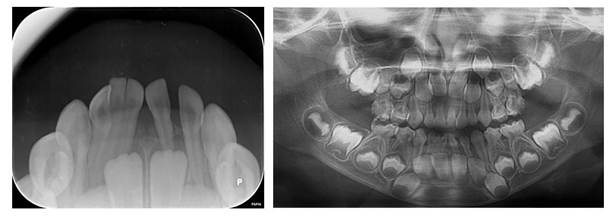

La radiografía intraoral evidenció la fusión de dos incisivos primarios derechos con un diente supernumerario, con la cámara pulpar y conductos radiculares separados; adicionalmente se observaron los incisivos centrales y laterales derechos e izquierdos permanente en proceso de formación. En la radiografía panorámica se observaron todos los gérmenes de los dientes permanentes en proceso de formación y no se evidenciaron anomalías dentarias en ellos (Figura 2).

Se efectuó una tomografía hemimaxilar en un equipo J. MORITA MFG con un voxel de 0.125 mm; el software utilizado fue i-Dixel. El informe de la radióloga indicó: “se observa pieza 8.1 y 8.2 fusionadas, pero además se observa fusión con pieza supernumeraria, las tres piezas están unidas por las coronas y las raíces, y cada una presenta su cámara y conducto radicular”. En el corte axial se observa la fusión a nivel de dentina de las tres piezas; en el corte tangencial se aprecian las cámaras pulpares y los conductos radiculares de cada uno de los tres dientes fusionados. En el corte transaxial se observa la posición lingualizada del incisivo permanente inferior derecho (Figura 3).